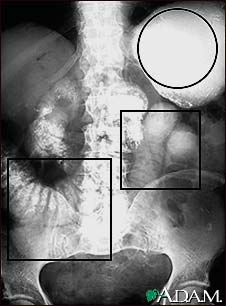

Ileus - X-ray of distended bowel and stomach

This abdominal x-ray shows a stomach filled with fluid and a swollen (distended) small bowel, caused by a blockage (obstruction) in the intestines. A solution containing a dye (barium) that is visible on x-rays was swallowed by the patient (upper GI series).